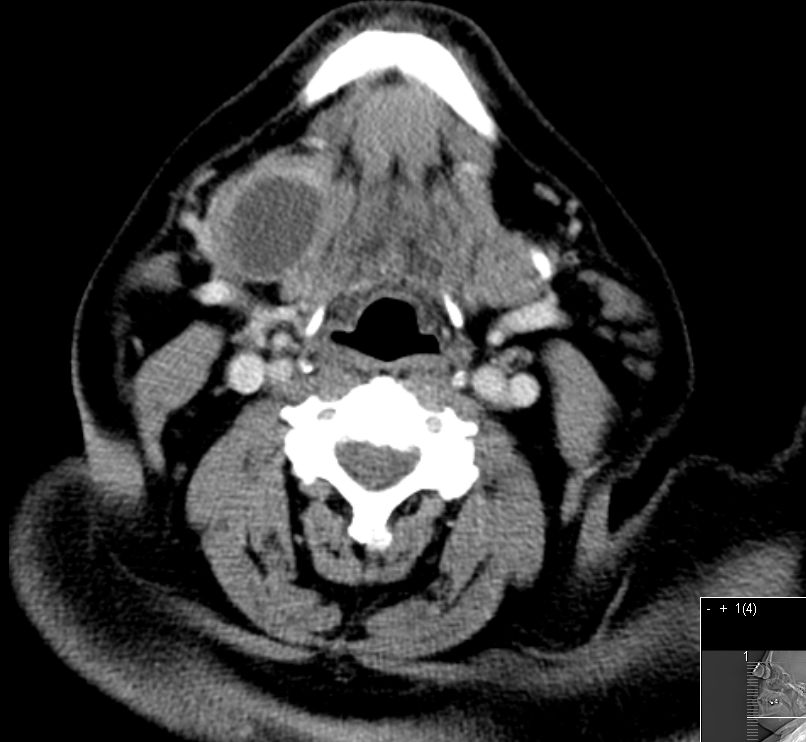

55-jähriger Mann mit einem Karzinom der linken G. submandibularis pT3 pNo Mo![]() |